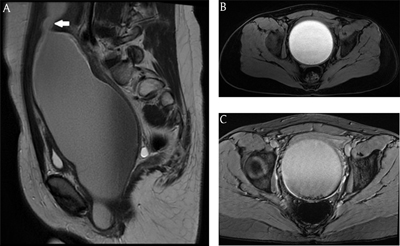

Figure 2

MRI: A. Sagittal T2-weighted image showing a large cystic mass with T2 hyper- to iso-intense content. Arrow = uterine cervix. B. Axial T1-weighted image showing a large cystic mass with T1 hyperintense content. C. Axial T2*-weighted image showing susceptibility artifacts posteriorly in the lesion.